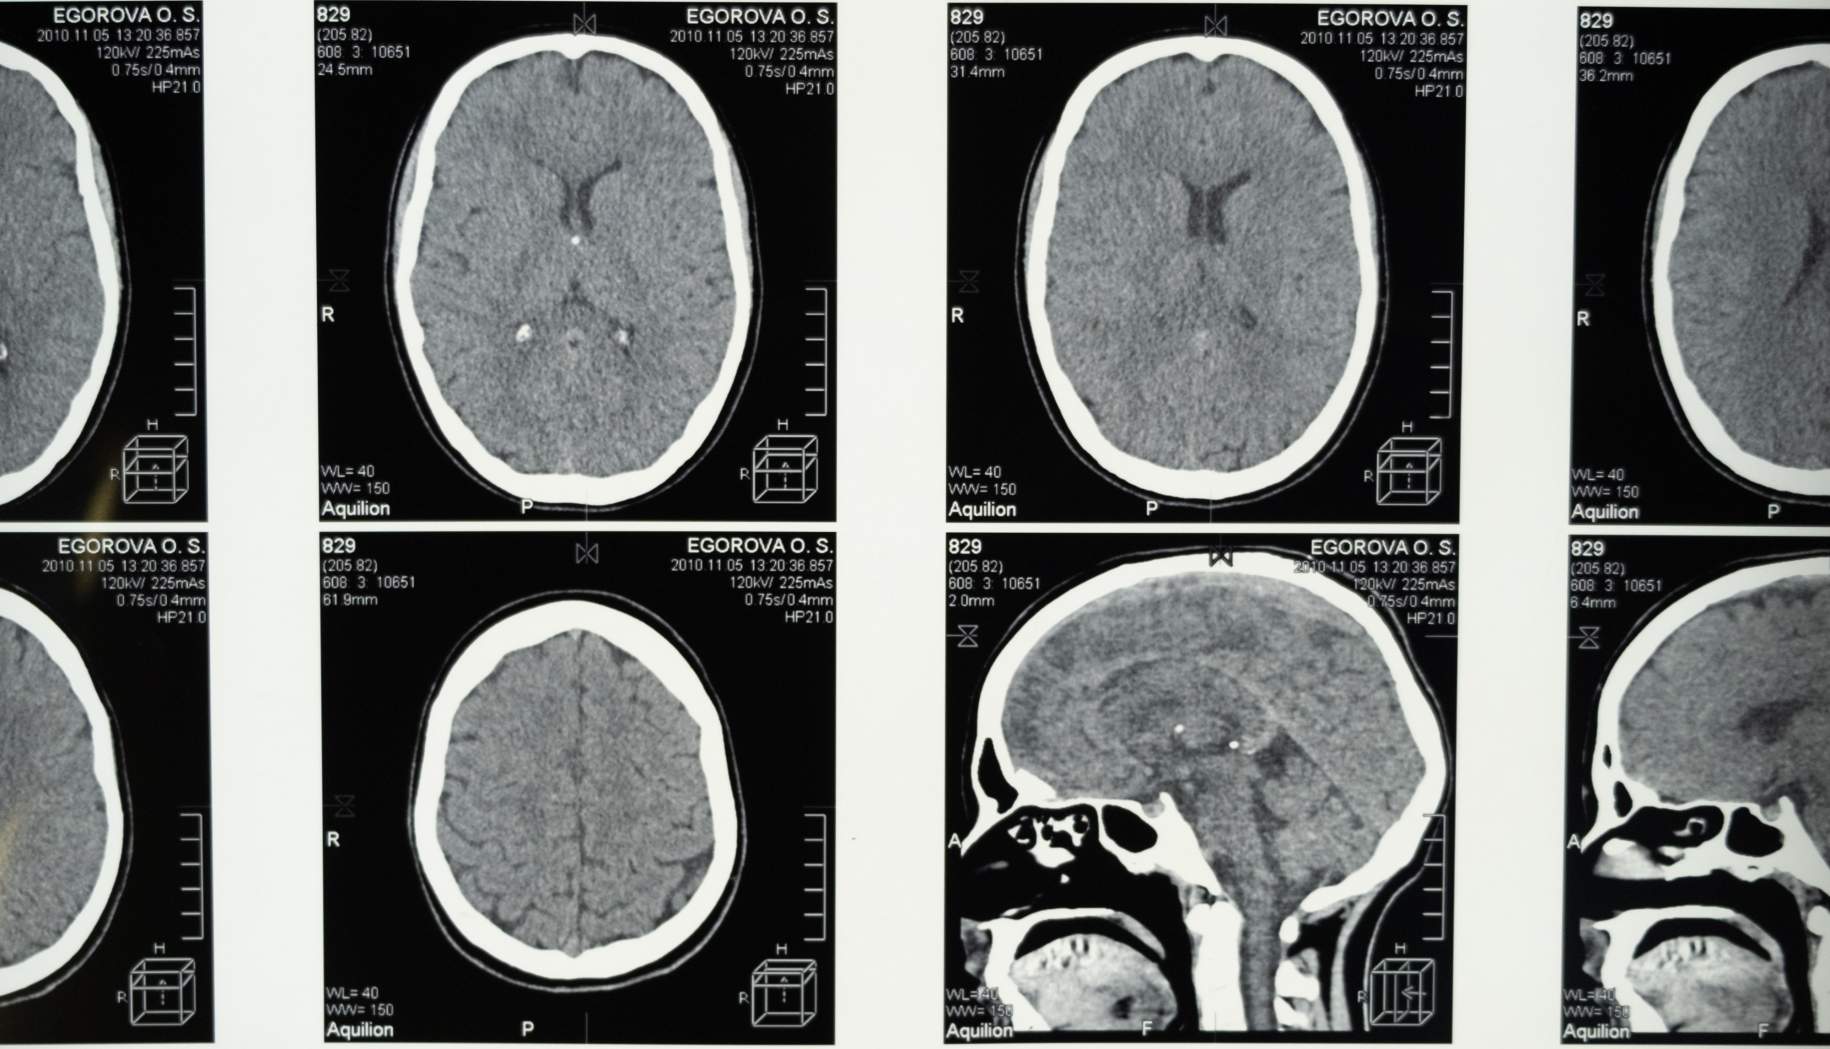

Figure 1. This illustration demonstrates a meningioma compressing the brainstem. An attempt at complete surgical removal is the best course of treatment.